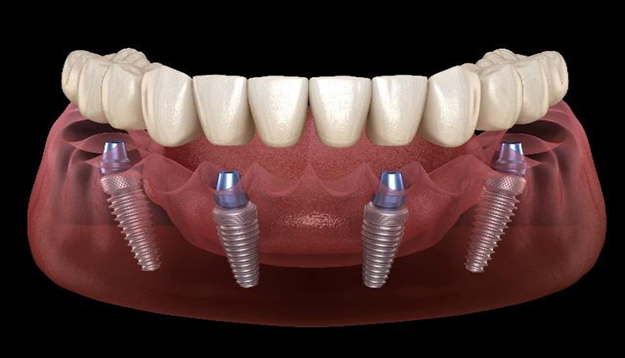

In the concept of All on four implants, there are 4 implants placed (2 in front side and 2 in Back side) in one jaw. Front 2 implants are placed straight whereas 2 back implants are placed tilted. With the help of 4 implants, you can get a minimum of 12 teeth in a single jaw which will help you to chew. That will also fulfill the purpose of esthetic (looks). Because of the position of All on four implants, we can avoid such surgical procedures. This is the biggest advantage in all on four implant procedures in terms of cost too since we are only exploiting a minimum 4 implants per jaw.